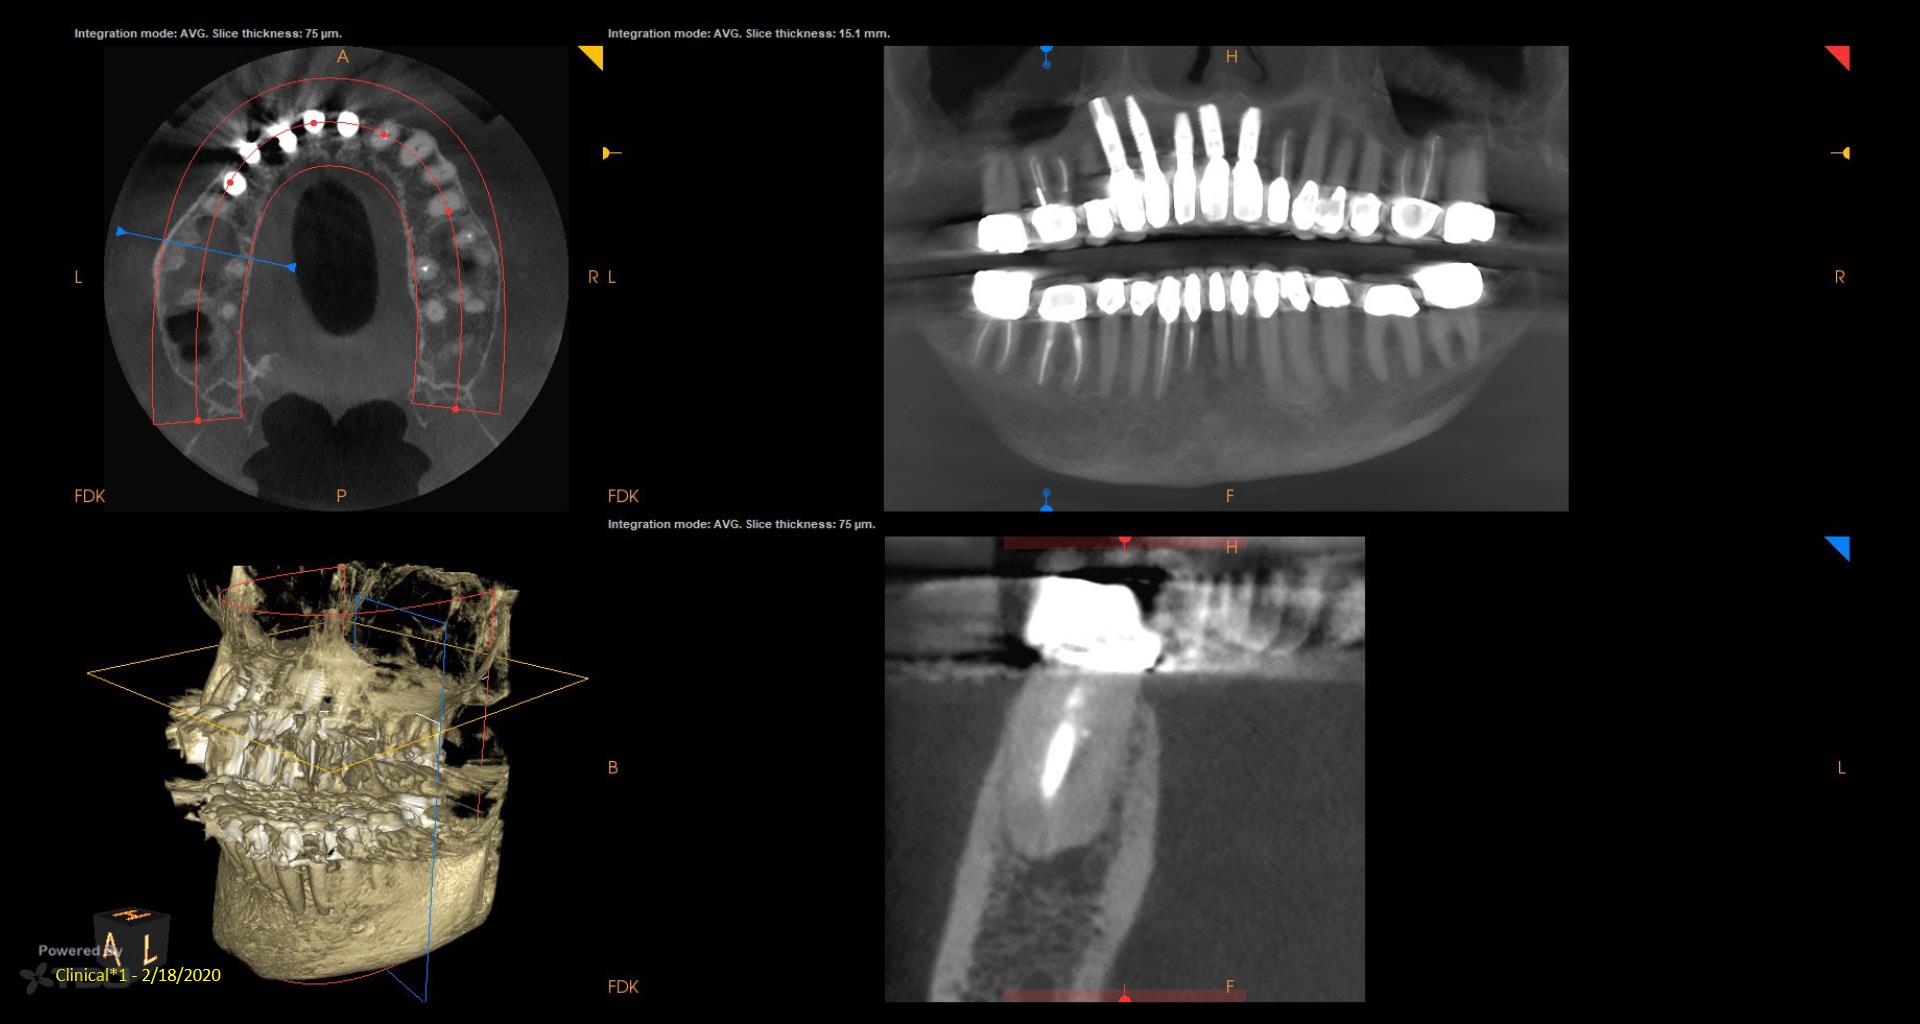

I did a retreat #19 15 years ago. Today symptom free but #18 looks suspicious and maybe even #19……. Perfect case for monitoring….not anxious to do another retreat… gbc

My experience with retreat #19 fifteen years ago was transformative, and I’m grateful to be symptom-free today. However, I’ve noticed convalescent hospital some concerning signs with #18 and possibly #19, which makes me cautious. While I appreciate the value of retreats, I’m not eager to dive back in just yet. Monitoring feels essential now.